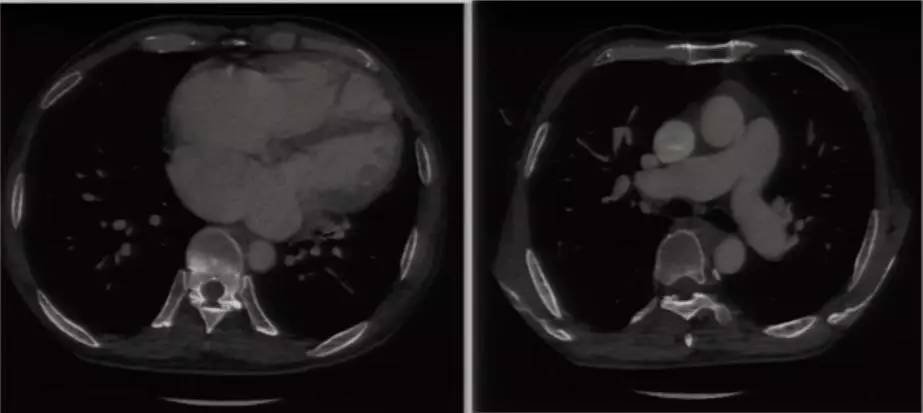

进一步完善相关检查:胸片提示双肺淤血,肺血增多,升主动脉及主动脉结增宽,肺动脉段平直,全心增大,心胸比0.63(图6)。复查超声心动图可见LA 58 mm,LV 53 mm,LVEF 60%,RV 41 mm;房间隔卵圆孔回声分离3 mm,后下部薄弱,探及数处回声脱落,大者约18 mm;二尖瓣前叶发育异常,收缩期瓣体向左房弯曲,致对合不拢。超声提示先天性心脏病(先心病)、Ⅱ孔型房间隔缺损(多发)、卵圆孔未闭、房水平左向右分流 ,二尖瓣脱垂并中大量反流,三尖瓣少中量反流,肺动脉高压49 mmHg。心脏CT提示先心病、房间隔缺损(下腔型),二尖瓣脱垂,双房右室扩大,少量心包积液(图7)。

图7